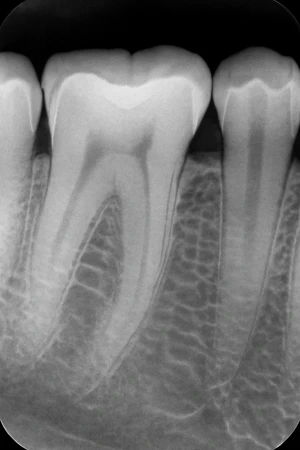

Pemeriksaan foto periapikal untuk mendapatkan gambaran lengkap kondisi akar dan jaringan sekitar gigi, membantu diagnosis yang lebih akurat.

Periapikal adalah jenis rontgen kecil yang dapat memberikan gambaran yang presisi pada 1-3 gigi yang bersebelahan. Rontgen gigi ini menggunakan sensor digital, maka hasil foto rontgen yang dihasilkan tampak lebih jelas.

Fungsi rontgen periapikal

- Menunjukkan panjang setiap gigi, dari mahkota hingga akar

- Melihat kondisi 1-3 gigi sebelum mengambil tindakan cabut gigi, perawatan saraf gigi, atau penambalan gigi

- Menemukan masalah gigi di bawah permukaan gusi atau dalam rahang, misalnya gigi bertubrukan, abses, kista, tumor, atau perubahan tulang akibat penyakit tertentu